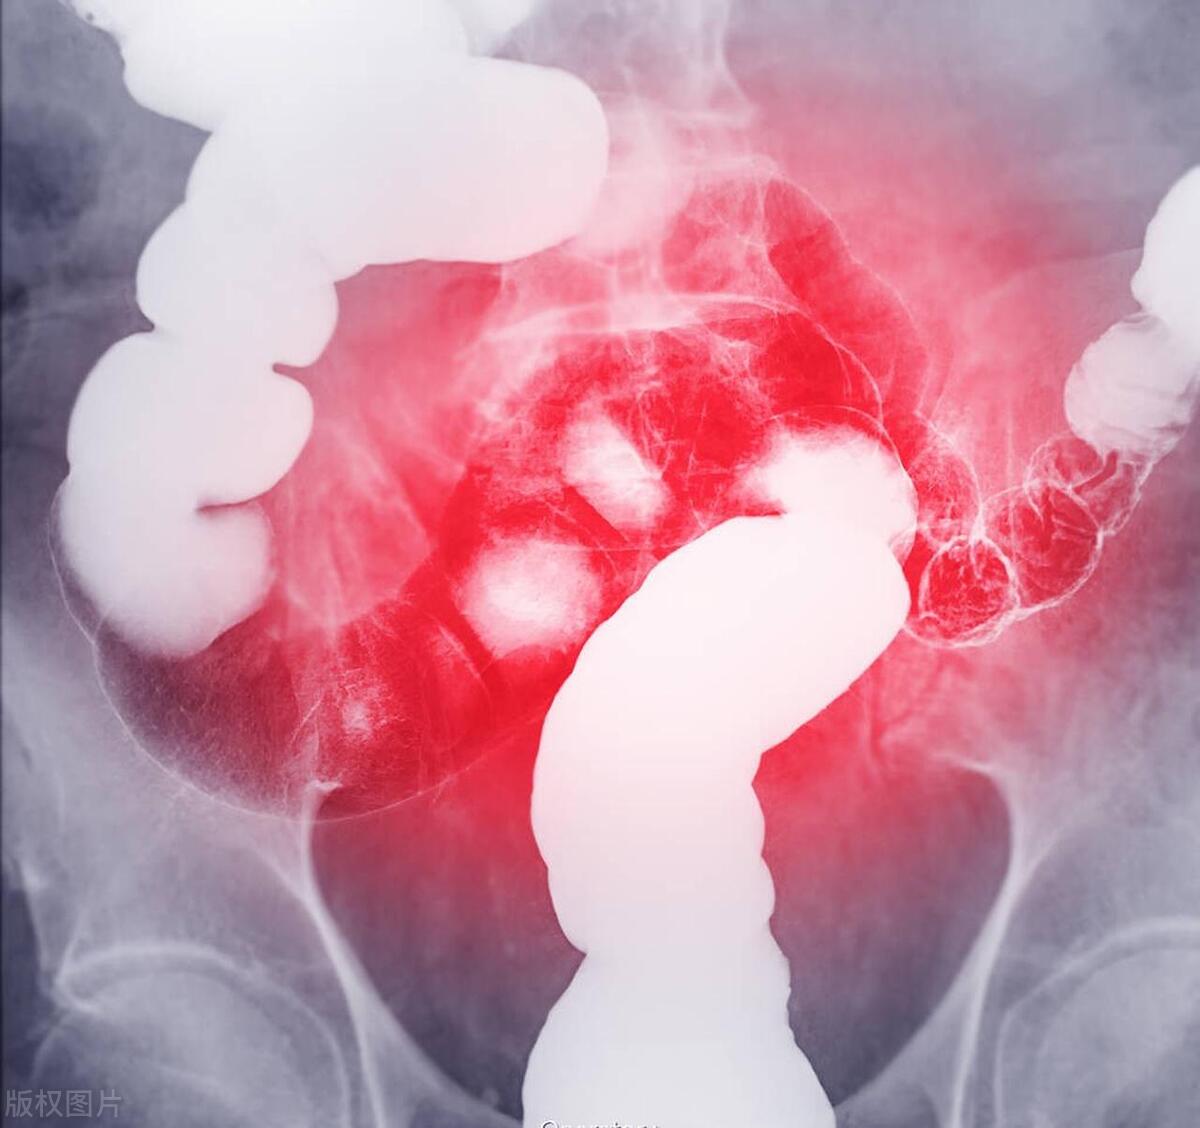

直肠癌:结直肠癌筛查一般采用粪便隐血试验和胃肠镜检查等形式。提议50岁及以上得人每一年进行一次粪便隐血试验或每五年进行一次胃肠镜检查。